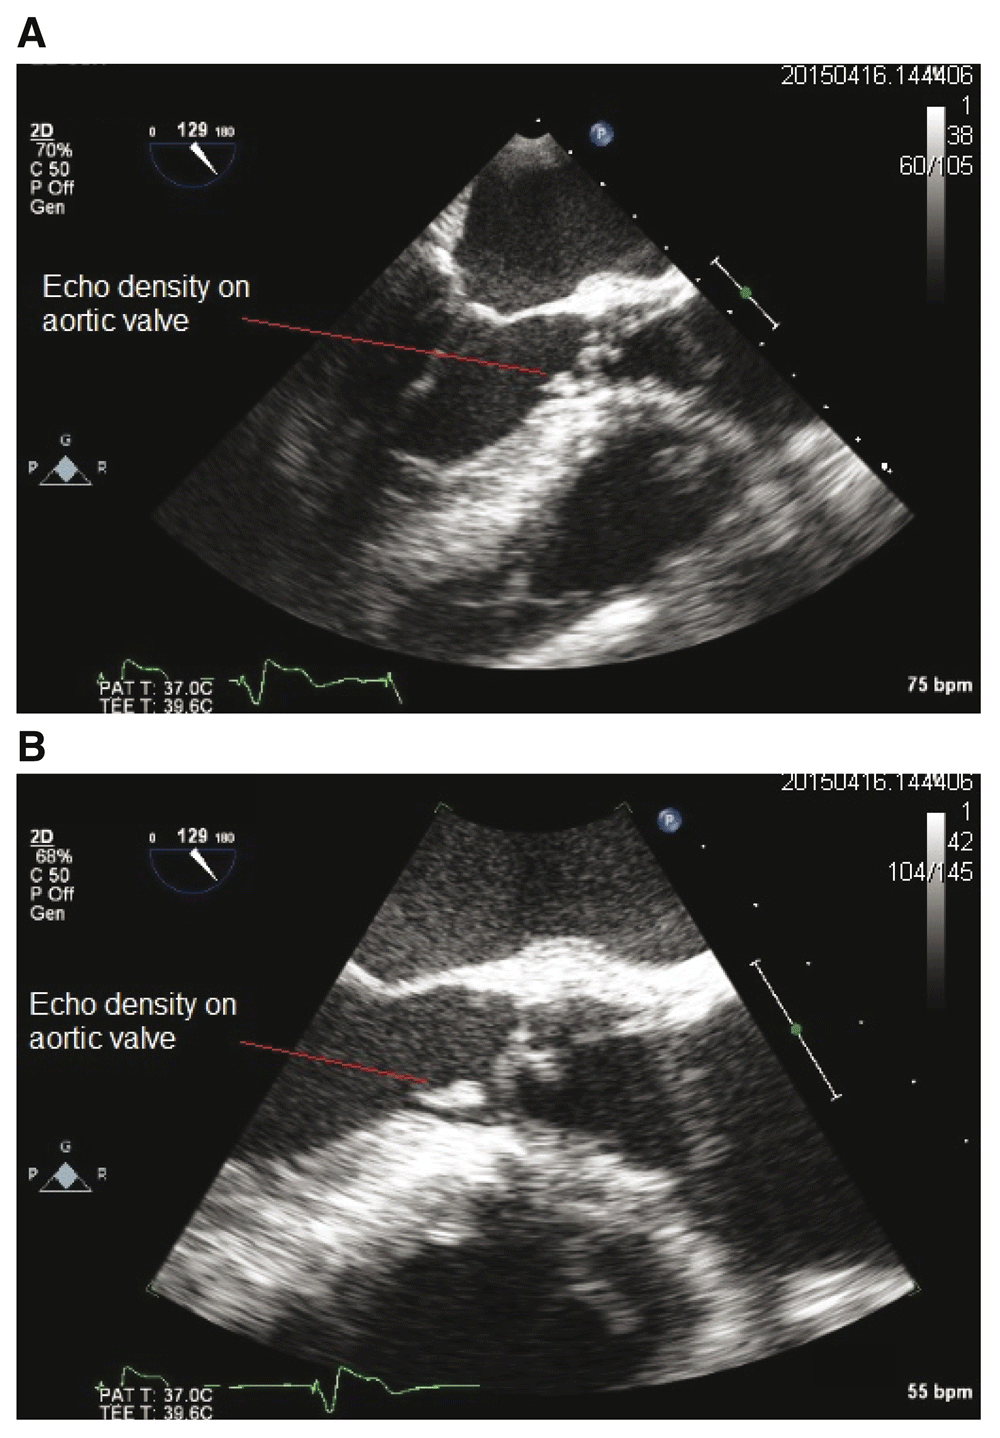

A trans-thoracic echocardiogram showed mild aortic regurgitation and mitral regurgitation with no clear vegetation, however, trans-esophageal echocardiogram (TOE) showed normal left ventricular function with moderate aortic regurgitation due to large mobile vegetation on the bio-prosthetic aortic valve. There was no peri-valvular abscess or features of the paravalvular abscess noted (See Image 1a and 1b). Pacemaker lead and right-sided valves were not involved.

1A: Transesophageal echocardiogram (TEE), mid-esophageal view showing mobile echo density on the prosthetic aortic valve. 1B: Transesophageal echocardiogram (TEE), mid-esophageal view enlarged to show mobile echo density on the prosthetic aortic valve.